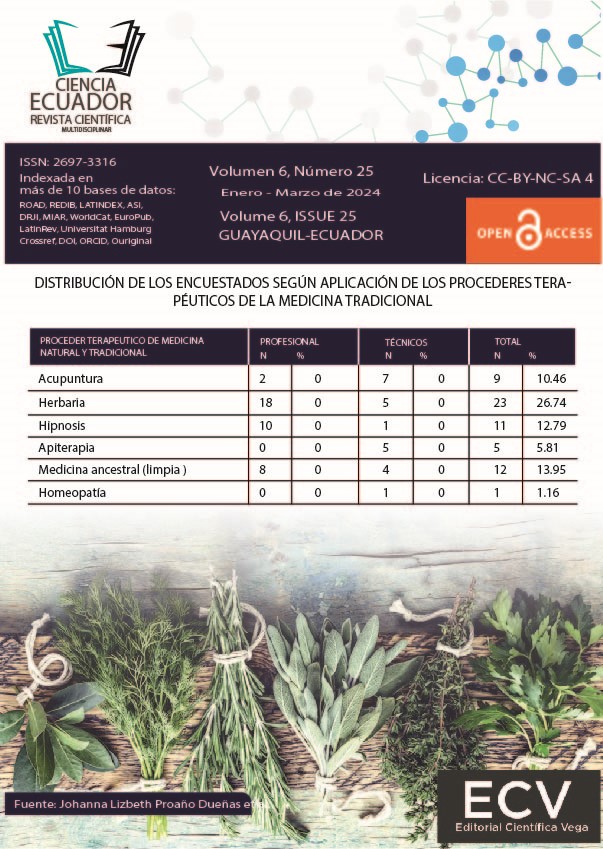

Herencia ancestral: La medicina herbaria y su utilización por parte del personal médico

Vol. 6 Núm. 25 (2024) -